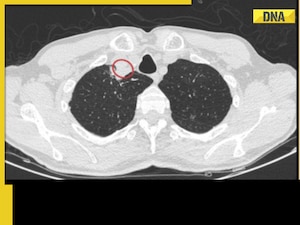

A "paratracheal abscess" in the man's neck, which was obstructing his airway and causing the symptoms, was discovered by a CT scan. He was given a daily antifungal medication prescription once the pus was drained.